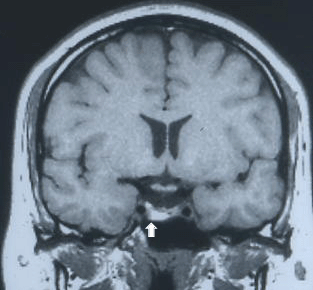

Lesions cerebrals. Com reduir els efectes?

Els estudis sobre el funcionament del cervell van desvetllant a poc a poc els seus grans misteris. Se sap, per exemple, que davant una lesió traumàtica s'activen certs mecanismes que intenten neutralitzar els seus efectes. Ara un grup de científics de la UAB ha...

Cervell